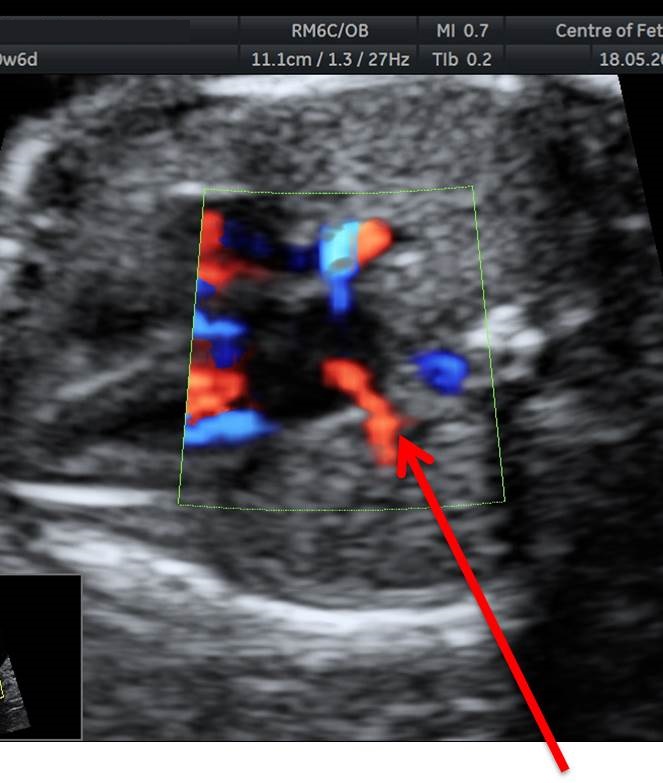

Вопрос 12

Поставьте диагноз

• А — норма;​

• Б — АВ-канал ;​

• В — коарктация аорты;

• Г — гипоплазия левого желудочка

Ответ на вопрос 12

• На 4камерном срезе сердца мы видим диспропорцию правого и левого желудочка с относительным уменьшением левого желудочка. Кровоток через митральный клапан сохранен, что позволяет исключить атрезию митрального клапана и гипоплазию левого желудочка

• В срезе через дугу аорты и дугу артериального протока мы видим, что перешеек аорты значительно меньших размеров по сравнению с артериальным протоком, что позволяет установить коарктацию аорты